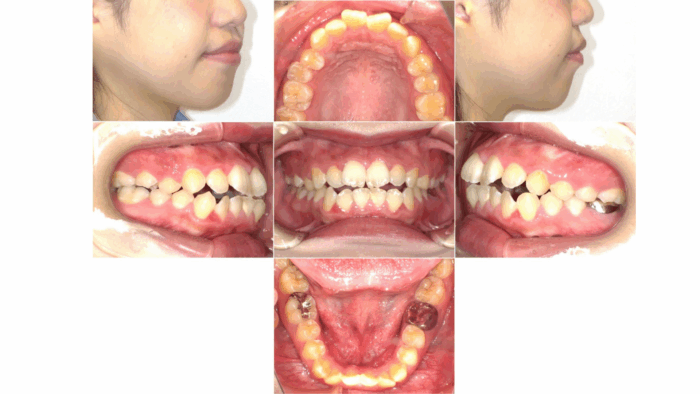

21歳、女性の患者さま。前歯が噛み合わないことに加え、横顔の見た目(口元の突出感)を気にされて来院されました。

◼︎診断

診察の結果、前歯が噛み合わない「開咬」に加え、口元が前方に出やすい状態が見られたため、かみ合わせと横顔のバランスの両方を改善できる治療計画をご提案しました。

今回の症例では、口元の突出感を改善するために、歯を後方へ移動させるスペースを確保する必要がありました。そのため、上下左右の小臼歯を1本ずつ、計4本抜歯しました。

ワイヤー矯正によって、まずは歯並びのガタガタを解消し、その後抜歯したスペースを利用して口元を下げて行きました。

■治療前後の変化

治療前は前歯にすき間があり、口元の突出感も見られましたが、治療後は前歯がしっかり噛み合い、口元がすっきりとした印象になりました。横顔のバランスも整い、より自然な口元へと変化しています。

主訴:前歯がかんでいないことが気になる

診断名:開咬

初診時年齢:21歳

装置名:表側矯正(ワイヤー)

抜歯部位:上下左右第一小臼歯

治療期間:1年9ヶ月

費用:税込810,000円

リスク・副作用:痛み、歯根吸収、歯肉退縮、虫歯、後戻り